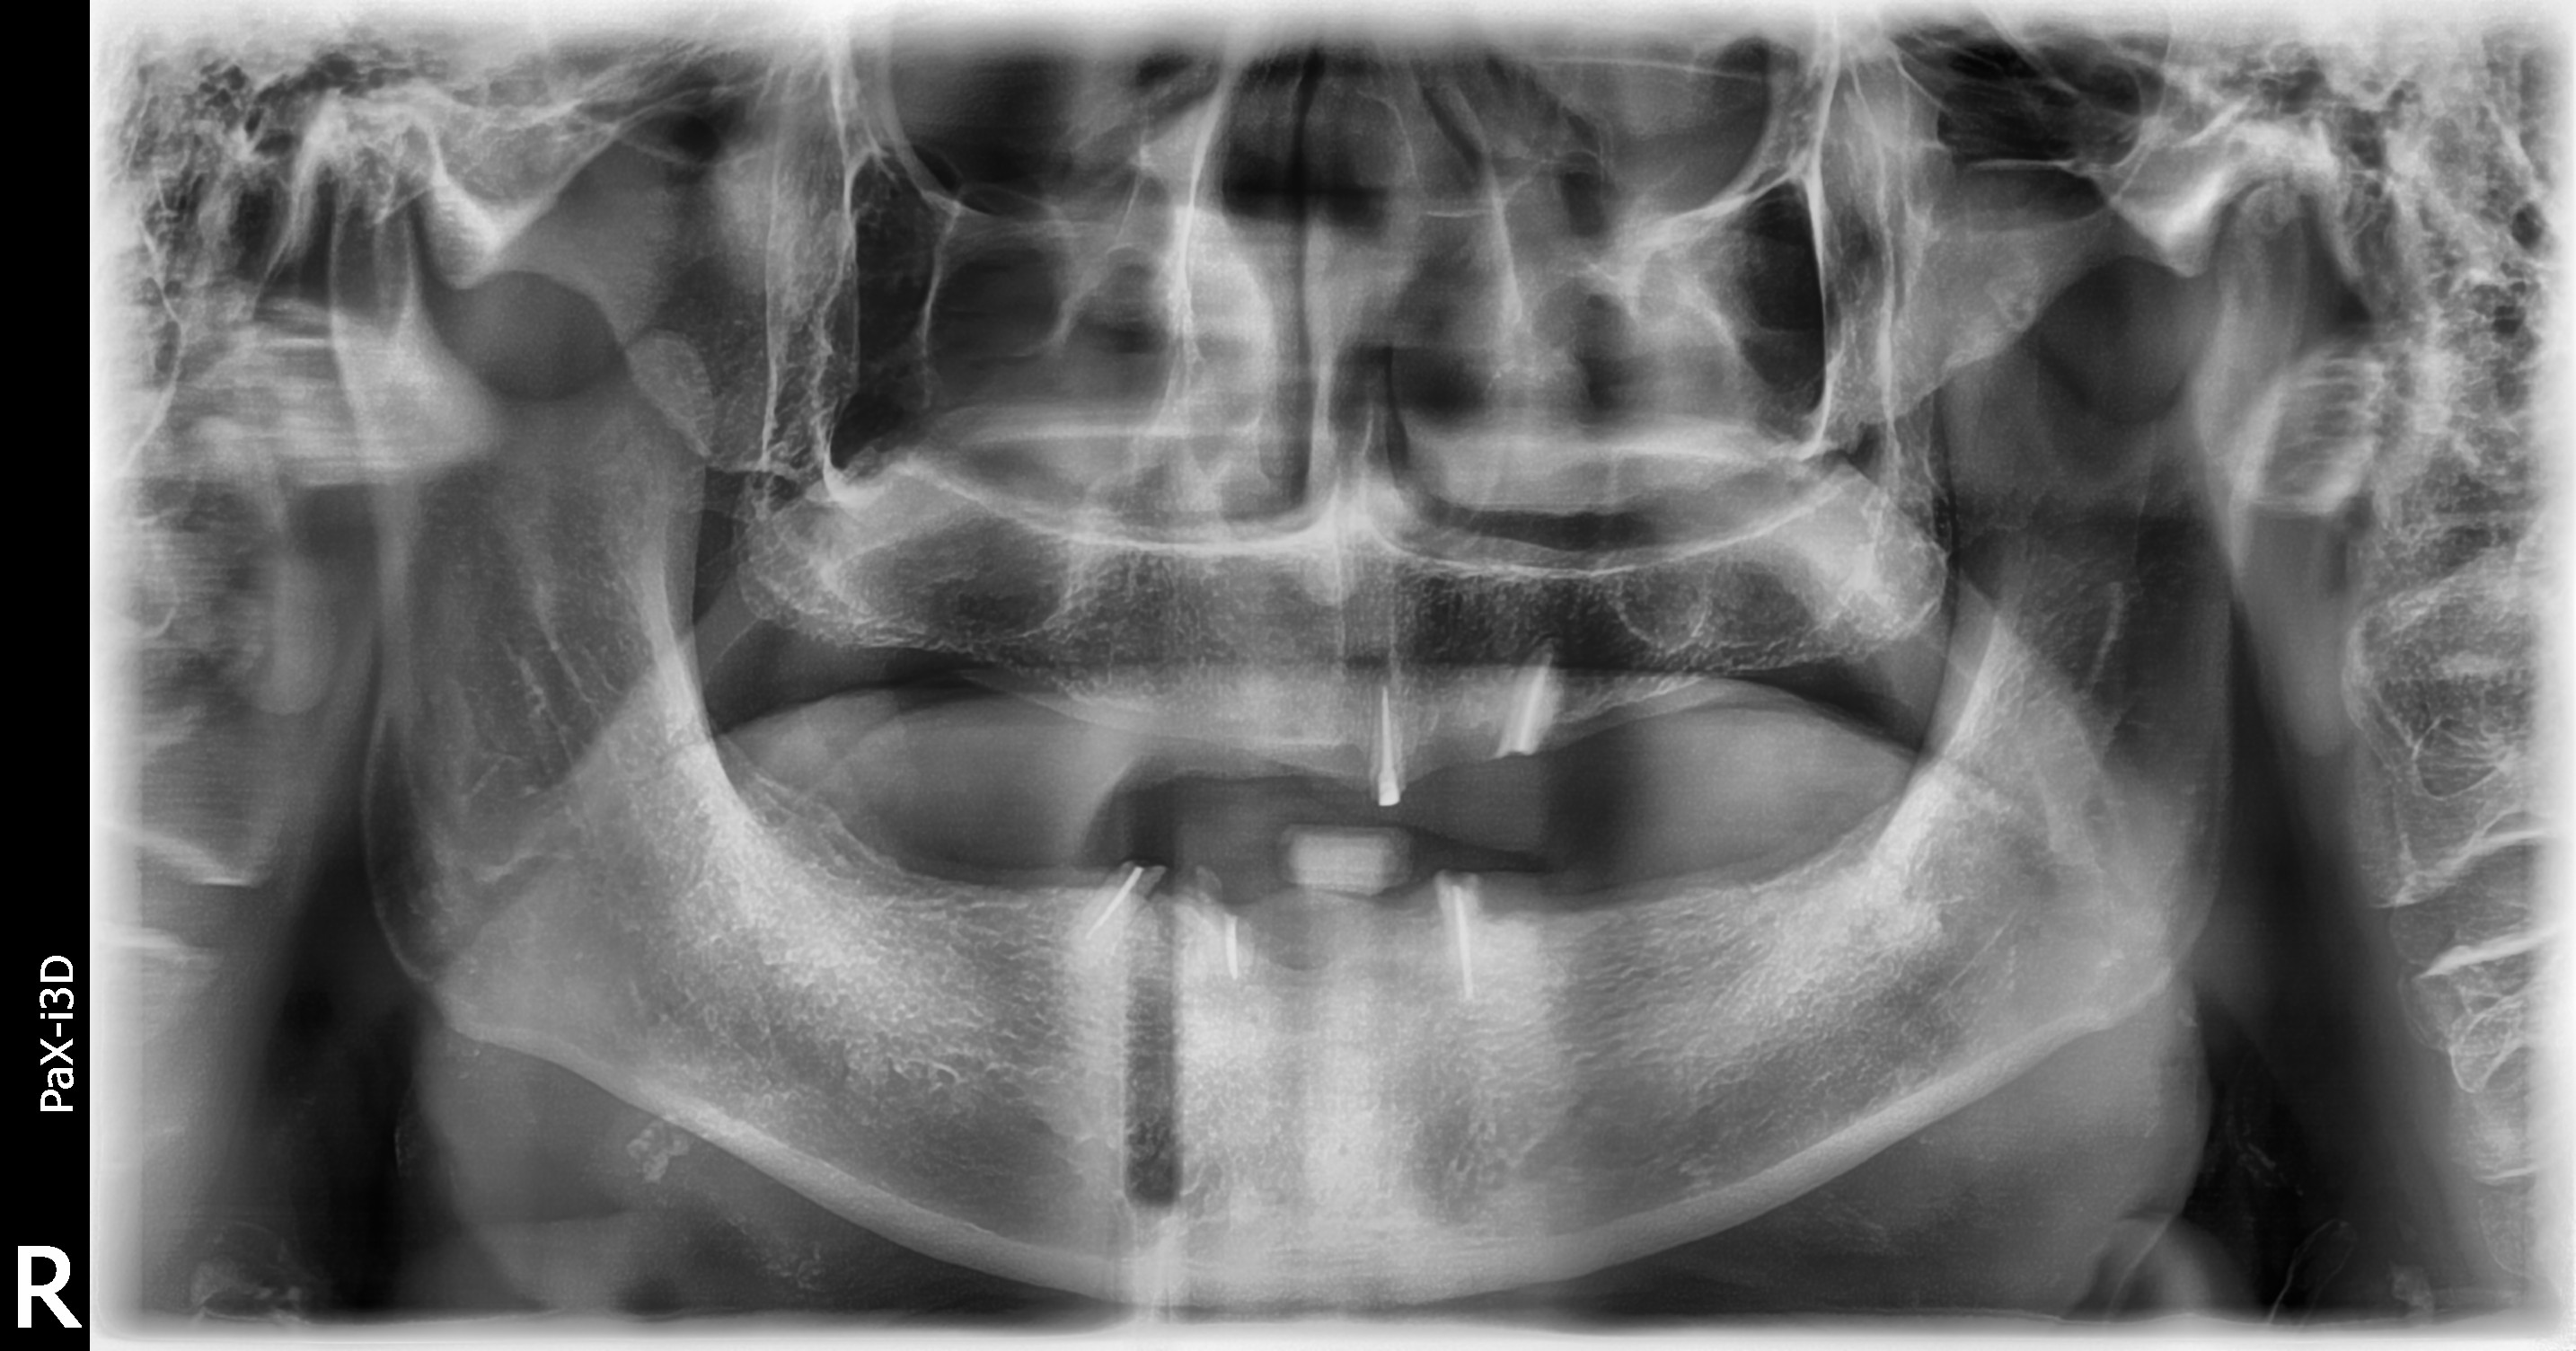

BEFOREAFTERBEFOREAFTER(식립)AFTER(착용)

임플란트 틀니